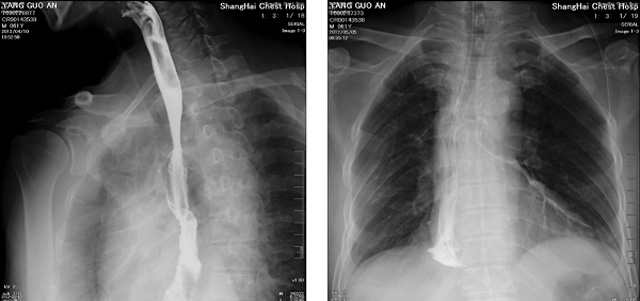

DR設(shè)備在2020年的新冠疫情中,加速了市場(chǎng)調(diào)整。以醫(yī)院為主的向二三級(jí)市場(chǎng)轉(zhuǎn)變。特別是小巧靈活的移動(dòng)DR設(shè)計(jì),填補(bǔ)CT和磁共振不能三維檢查的缺點(diǎn),滿足內(nèi)科外科特別是骨科的影像診斷需求。還有懸吊DR設(shè)備CT斷層射線系統(tǒng)。使用錐束成像技術(shù)對(duì)整個(gè)脊柱和整個(gè)下肢進(jìn)行了體積三維掃描。無需使用對(duì)比劑,即可使用X射線呼吸功能標(biāo)測(cè)來模擬模擬氣流和血流,以評(píng)估患者的肺動(dòng)脈血栓。

數(shù)字化X線攝影依然是患者初篩的關(guān)鍵一環(huán)。靜態(tài)DR限制于探測(cè)器平臺(tái)。只能進(jìn)行簡單普通的數(shù)字化影像檢查。胸部的疾病沒辦法篩查出微小的病灶。這樣導(dǎo)致DR慢慢的被CT跟磁共振代替。這樣造成了原來配套的數(shù)字化影像DR設(shè)備的 閑置。所以DR需要跟CT融合擴(kuò)大DR的檢查使用場(chǎng)景。為DR提高更多的市場(chǎng)價(jià)值。X射線技術(shù)的原始形式和面向未來的可能性打破了CT成像和DR成像掃描技術(shù)之間的限制。融合成像趨勢(shì)更加明顯,多峰成像趨勢(shì)發(fā)展更加迅速。